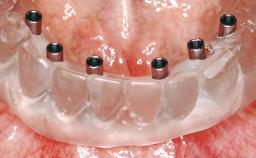

Conventional Loading of Eight Implants in the Maxilla and Final Restoration with a Full-Arch Gold-Ceramic FDP

A 35-year-old Caucasian female presenting with advanced periodontal disease involving both the maxillary and the mandibular dentition was referred for evaluation. The patient, a non-smoker in good general health, requested treatment for recurrent periodontal abscesses, tooth mobility, and discomfort during chewing, as well as restoration of her missing teeth with a fixed prosthesis to improve mastication and esthetics. All residual maxillary teeth exhibited plaque deposits, deep pockets, bleeding on probing, and class III mobility and were evaluated as hopeless. All residual mandibular teeth except tooth 37 could be maintained after periodontal therapy.

# of Implants 8

Type of Implants One-Piece

Defining Characteristics Fully edentulous upper jaw to be rehabilitated with four or more implants